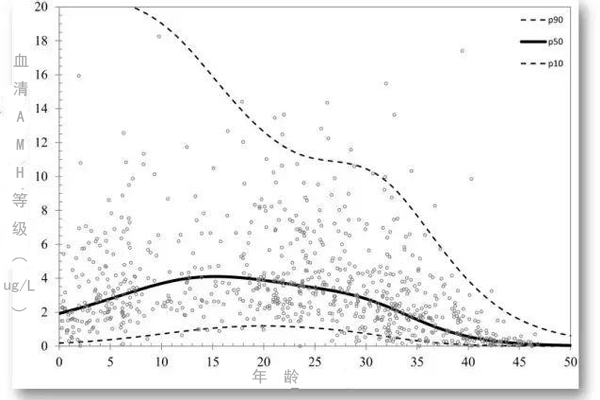

窦卵泡实际上是卵泡发育过程中发挥承上启下作用的关键环节,与窦卵泡相关的总窦卵泡计数(tAFC)则是评估卵巢储备功能以及评估IVF技术妊娠结果的重要指标。tAFC越...

获得一定数量的优质胚胎是试管婴儿治疗成功的关键,因此获得高质量的卵子是目前临床控制性超促排卵(Controlled ovarian hyperstimulatio...